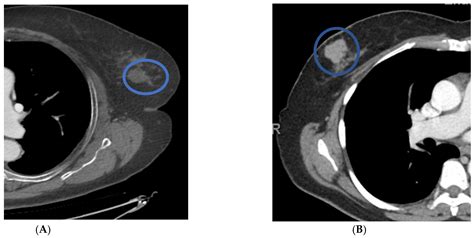

• Lung Cancer: Early detection of lung nodules or masses.

Advancements in technology have led to the development of advanced techniques in CT of thorax, enhancing the diagnostic capabilities. Some of these techniques include:

• High-Resolution CT (HRCT): Provides detailed images of the lung parenchyma, useful for diagnosing interstitial lung diseases.

• CT Angiography: Uses contrast dye to visualize blood vessels, aiding in the diagnosis of conditions like pulmonary embolism.